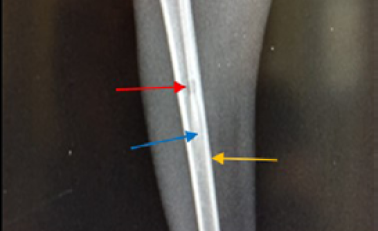

Site of operation, 14 days post treatment with Staph specific –bacteriophage given intramuscularly (Group C). Signs of osteomyelitis had disappeared. (Medullary canal is clear), bone cortex uniformed, normal bone density, the hole still present (ML View)

Site of operation, 14 days post treatment with Ceftaroline given intramuscularly (Group D). Still the medullary canal is not clear. Thickened cortex (→) and Endosteal reaction appeared clearly (→) (ML View)